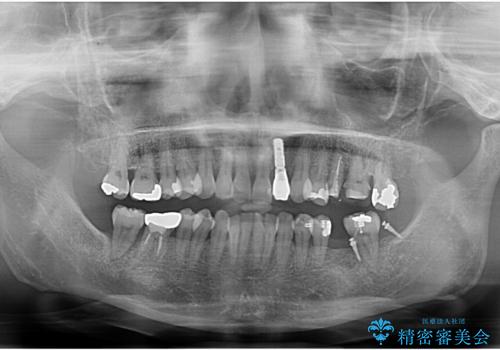

奥歯の部分矯正を行うことで、歯の傾きが良くなり、結果神経を取らずにブリッジを入れていくことができました。

通常矯正治療後は歯並びが戻らないように保定が必要ですが、ブリッジを入れているので歯並びは戻らないため保定が不要です。

部分矯正と補綴の相性は良いといえます。